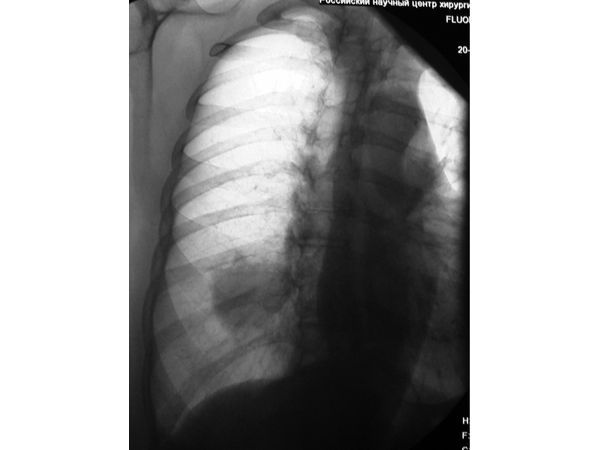

Согласно анамнезу, во время одного из плановых профилактических обследований, где делалась рентгенография, у женщины в нижней доле правого лёгкого впервые обнаружилась тень новообразования. В связи с этим она обследовалась в противотуберкулёзном диспансере, где стало ясно, что это не инфекционное заболевание. Пациентке не предложили хирургическое лечение, только наблюдение.

Через год и три месяца женщина проходила обследование в кардиологическом стационаре по поводу ишемической болезни сердца, постинфарктного кардиосклероза, стенокардии, а также нарушения углеводного обмена — сахарного диабета. Здесь вновь был сделан рентген органов грудной клетки и обнаружилось, что тень новообразования лёгкого увеличилась. Врачи приняли решение не проводить запланированную коронарографию, а сразу отправить пациентку в онкологический стационар, где снова был поднят вопрос о хирургическом лечении. Однако в операции было отказано из-за имеющихся у женщины сердечных заболеваний.

По результатам компьютерной томографии органов грудной клетки, на границе сегментов S9-S10 имелось мягкотканное образование с чёткими неровными контурами, прилегающее к костальной плевре. На фоне этого образования дистальные бронхи просматривались не фрагментарно. Увеличения внутригрудных лимфатических узлов не наблюдалось.